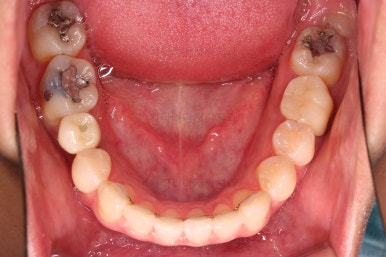

초진 시 입안의 모습입니다.

화살표는 결손 부위, 동그라기믄 유치잔존과 매복치아 부위입니다.

동그라미는 유치가 있는 상황이었는데요. 잇몸도 많이 파괴되어 있었고, 유치 자체의 상태도 좋지 못했어요.

동그라미 부분은 상한 유치가 보이는데, 그 하방으로 영구치가 매복되어 올라오지 못하고 있는 상태였어요.